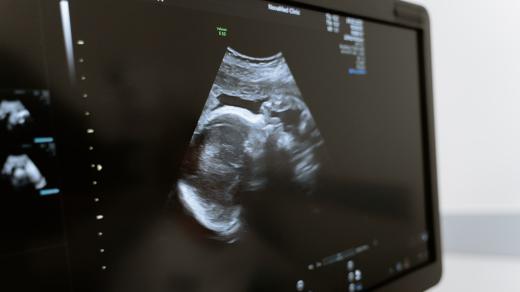

Ambulance porodních asistentek v nemocnici v Písku | Foto: Kristýna Barchini, Český rozhlas

Masáž rebozo šátkem, náprava polohy miminka nebo klidný rozhovor o porodu. To všechno nabízí nová ambulance porodních asistentek v Nemocnici Písek. Vznikla pro ženy, které chtějí poznat prostředí porodnice i personál ještě před porodem. Pokud je těhotenství bez komplikací, můžou se v posledním měsíci obracet už jen na porodní asistentku. Ta s nimi probere vše důležité a zařídí potřebná vyšetření.